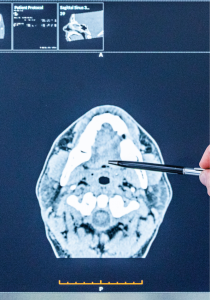

The term head and neck cancer includes a range of different cancers that originate from the head and neck. Most head and neck cancers originate from a tissue called squamous epithelium which lines the inside of the mouth, nose and throat.

Head and neck cancer includes:

- Nasal and paranasal sinus cancer (cancer originating from the tissue that lines the inside of the nose and sinuses)

- Oral cancer (cancer of the mouth)

- Salivary gland cancer

- Pharynx cancer (cancer of the throat, which is divided into 3 regions – the nasopharynx, the oropharynx and the hypopharynx)

- Larynx cancer (cancer of the voice box)